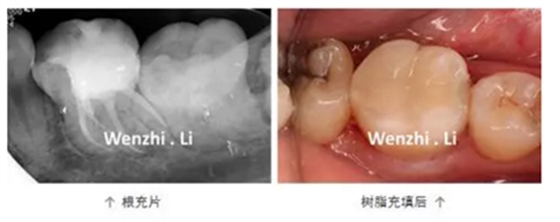

年輕女性患者因左下后牙間斷性自發(fā)性疼痛及冷熱刺激痛1個(gè)月就診,診斷為36慢性牙髓炎。局麻下,橡皮樟隔離下去腐,開髓,揭頂,可見髓腔鈣化,顯微鏡下超聲去除鈣化物,探及4個(gè)根管口,拍攝初尖銼片顯示MB根管為重度彎曲根管、DL根管彎曲極近根尖區(qū),X線片上未顯示。17% EDTA配合PathFile、Protaper NEXT 鎳鈦器械預(yù)備根管,實(shí)現(xiàn)連續(xù)錐度的根管形態(tài),5.25% NaClO沖洗,連續(xù)波熱牙膠根管充填4個(gè)根管,拍攝根充片,X線片顯示根充恰填。隔濕干燥,自酸蝕粘接,SDR+納米樹脂充填。

2. 預(yù)備彎曲根管技巧:器械預(yù)彎,建立直線通路;使用柔韌性及抗疲勞強(qiáng)度更好的鎳鈦旋轉(zhuǎn)器械;足量及有效的超聲根管蕩洗;連續(xù)波加壓充填技術(shù)。PathFile柔韌性好,在足量根管潤滑劑下,可以順暢的通過根管彎曲部。Protaper NEXT 具有較好的柔韌性及抗疲勞強(qiáng)度,可降低預(yù)備彎曲根管時(shí)出現(xiàn)根管偏移的風(fēng)險(xiǎn)。